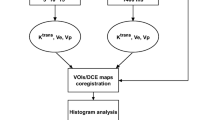

Differential maps

Differential T1 relaxation time maps (DiffT1) and T2 relaxation time maps (DiffT2) were generated according to the method of Ellingson et al. 2012 [28]. These maps are generated by registering the T1 or T2 maps of two time points followed by a voxelwise subtraction of the T1 or T2 relaxation times, respectively. Time-point one, the baseline, was the first MR scan after initiation of bevacizumab therapy in order to detect new tumor progression in the follow-up scans. Each map of a follow-up time point (n) was hence subtracted from the baseline (time-point one). We used linear registration with FLIRT (the FMRIB Linear Image Registration Tool of the Functional Magnetic Resonance Imaging of the Brain facility; Jenkinson, 2012) [29].

Subtraction maps

The maps should indicate the shortening of T1 relaxation time upon the accumulation of contrast agent within the tumor tissue. The T1 relaxation time maps which were acquired before application of contrast agent were coregistered with the contrast-enhanced T1 relaxation time maps of the same MR examination and then a voxelwise subtraction according to the formula ((T1-pre-CA − T1-post-CA) / T1-post-CA) was performed (Fig. 1, lower row).